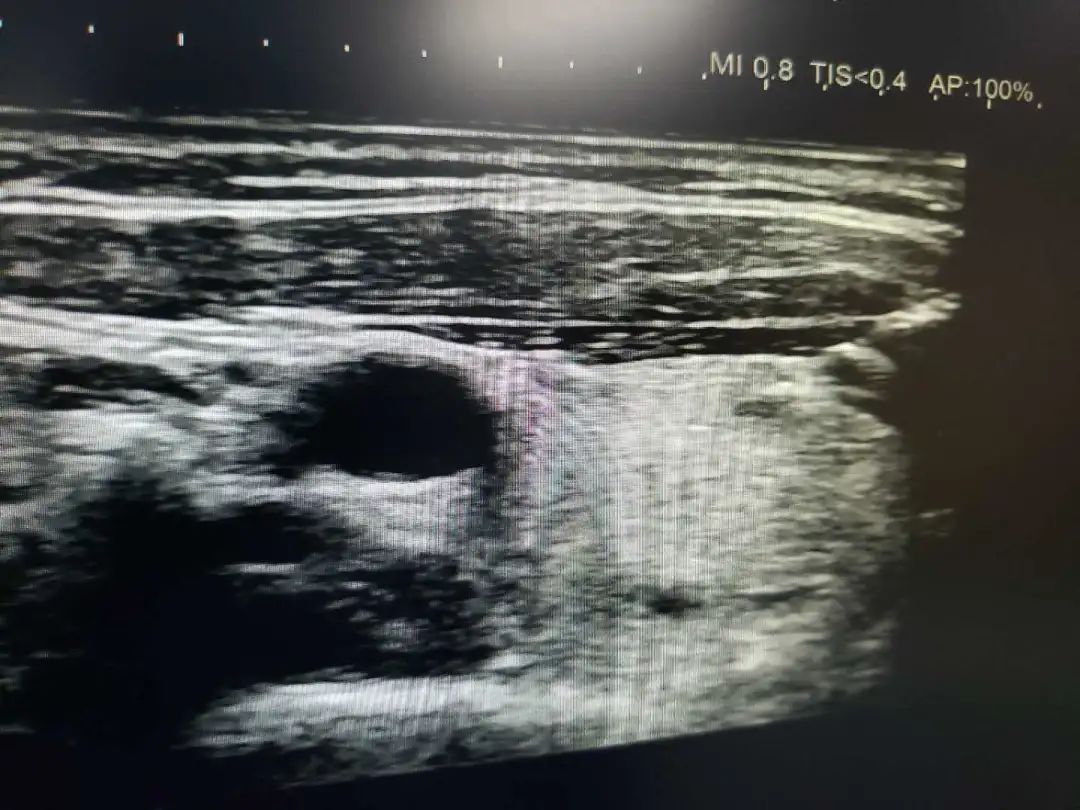

诊断是治疗的前提,正确的诊断,相当于成功了一半,活检则是确诊的唯一金标准。超声介入活检适用于全身各部位软组织的活检,如淋巴结、甲状腺、乳腺等。

适用于肝囊肿、肾囊肿、甲状腺囊肿等囊性病变。在超声引导下,用一根细针,直接经皮肤进入囊肿内,抽尽囊液,注入特殊药物,拔出细针便能治好。整个治疗过程仅需30-60分钟,经过数月,囊肿慢慢吸收。